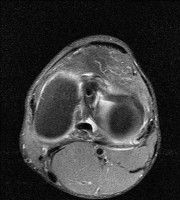

무릎 mri 간단히 봐주실 수 있으시나요 ㅠㅠ

안녕하세요 8년전 십자인대 수술하고 최근 무리한 운동에 무릎 불편감이 생겨서

mri 찍었습니다.

진단결과는 첫 찍은 병원에서 활액막염 이라는 진단을 받았습니다. 혹시 봐주실 수 있으실까요?

올라온 MRI가 단편적이라서 정확한 진단에 어려움이 있지만 십자인대에는 큰 이상이 있지는 않은것 같으며, 무릎관절내 물이 있는 것으로 보아 활액막염의 진단이 맞을 것 같습니다.

하지만 단편적인 영상이기 때문에 촬영병원에서 정확한 판독지 등을 받으시는 것이 좋겠습니다.